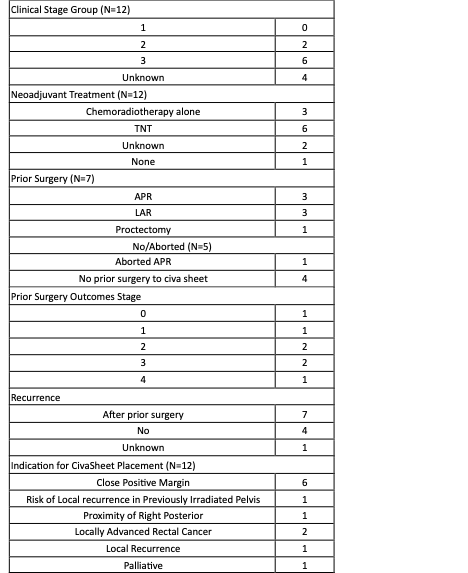

Figure 1. CivaSheet placement and fixation within the pelvis following pelvic exenterationTable 1. Patient and cancer characteristics of those who underwent CivaSheet placement 2017-2025.

Table 1. Patient and cancer characteristics of those who underwent CivaSheet placement 2017-2025.

Table 1. Patient and cancer characteristics of those who underwent CivaSheet placement 2017-2025.